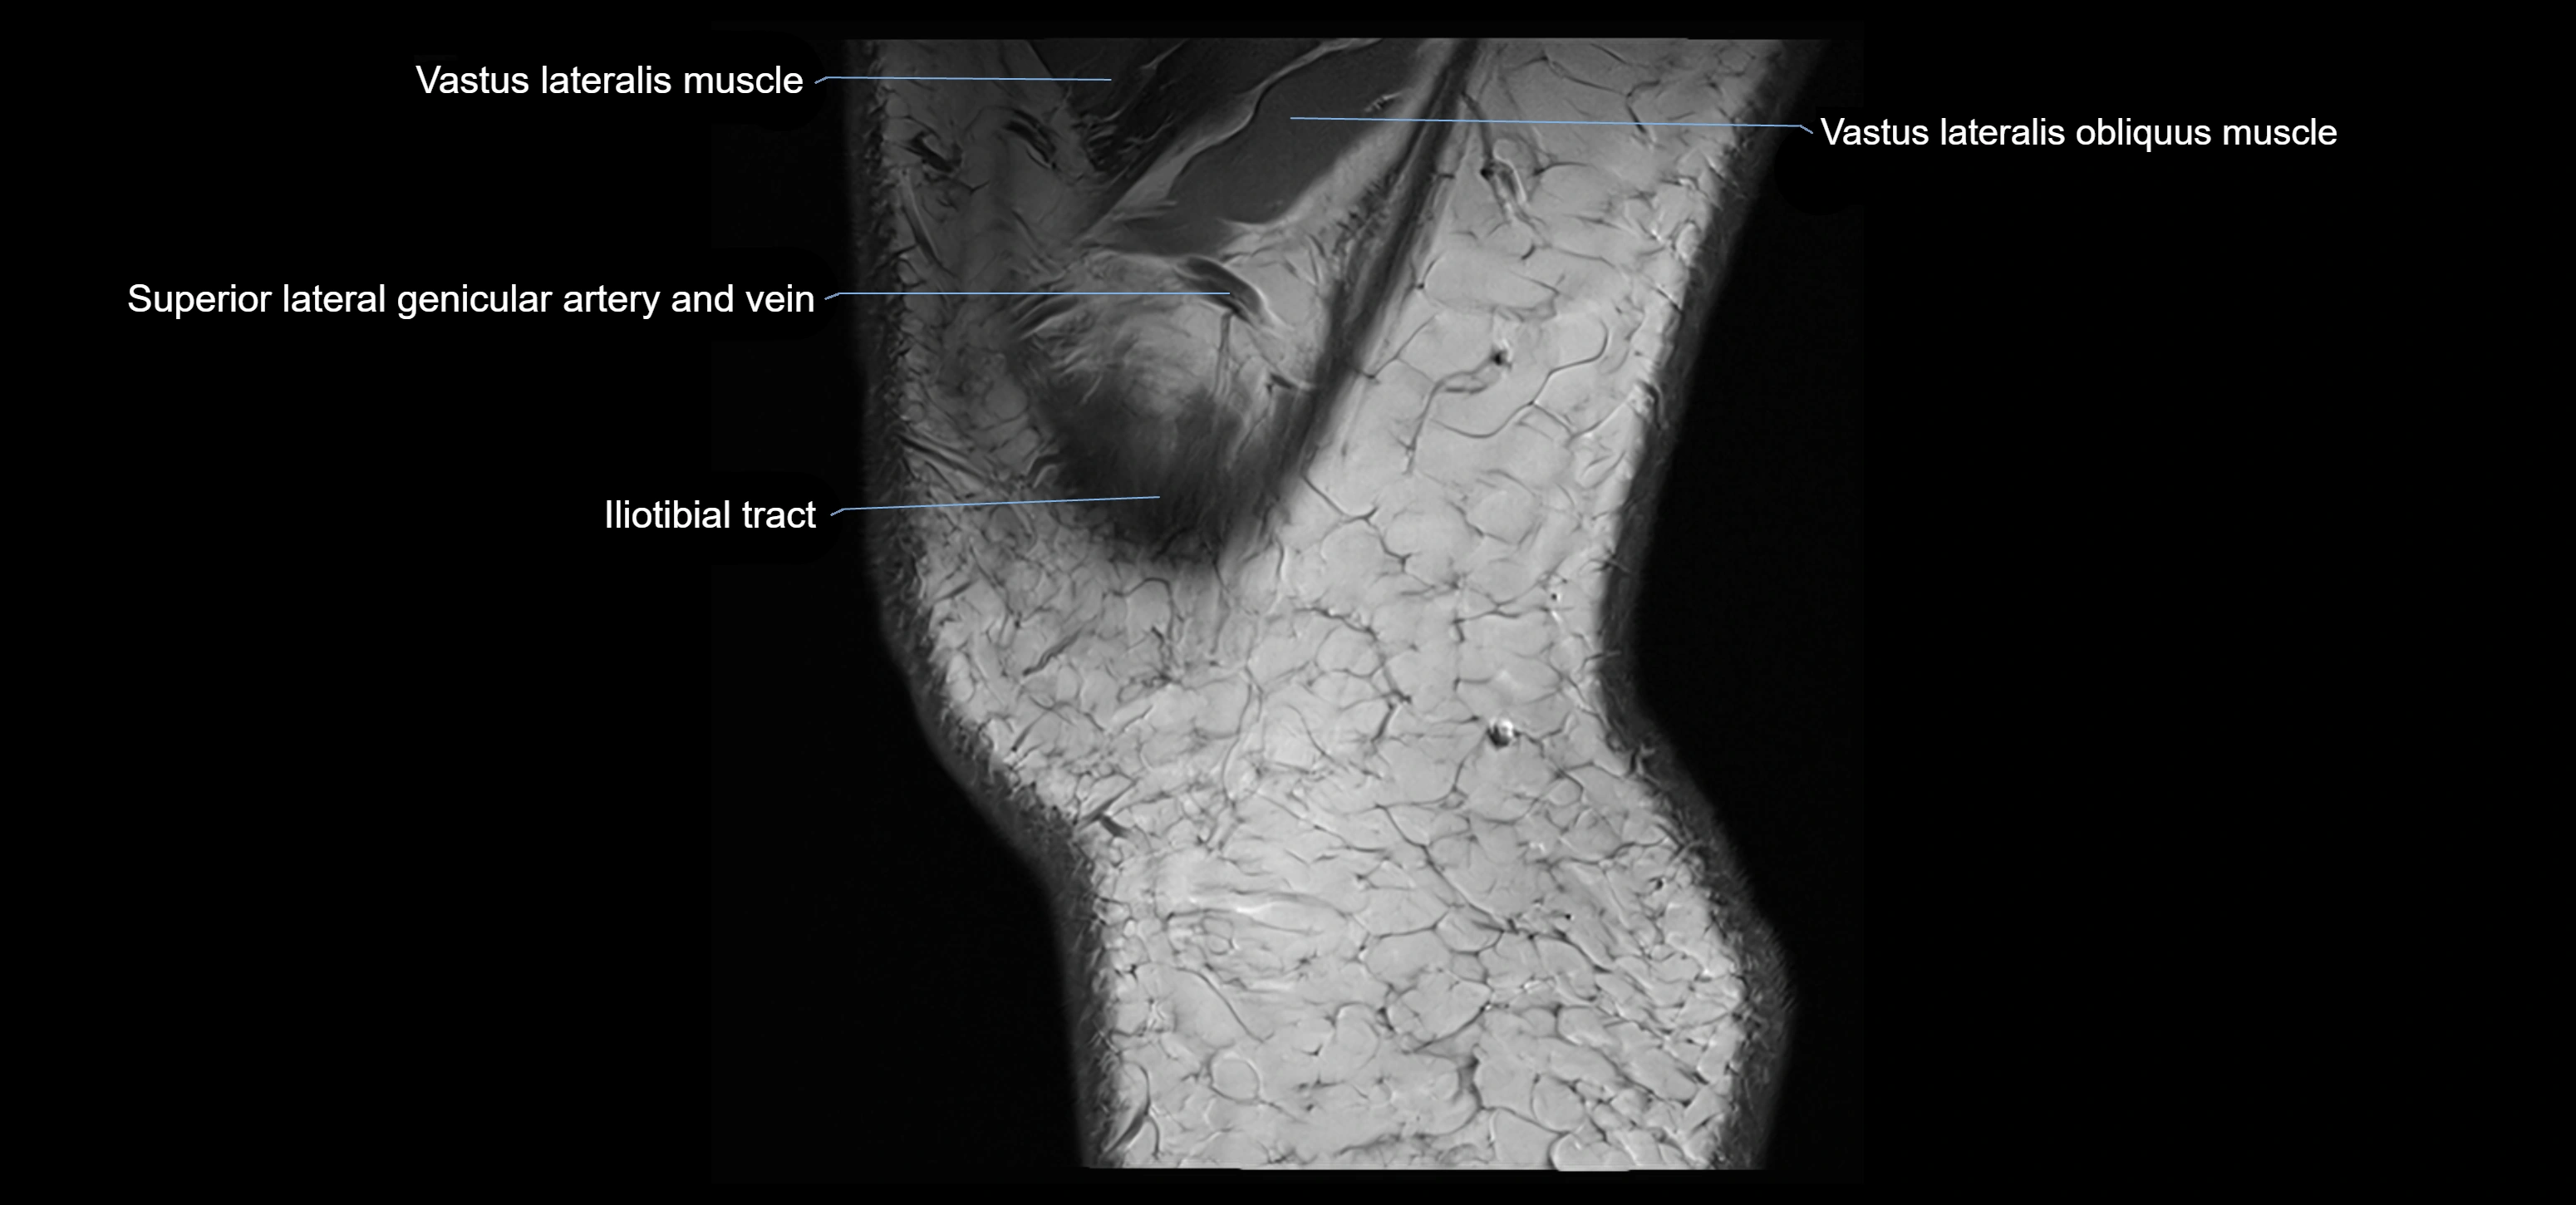

- Vastus Lateralis Obliquus Muscle

- Vastus lateralis muscle

- Superior lateral genicular artery

- Superior lateral genicular vein